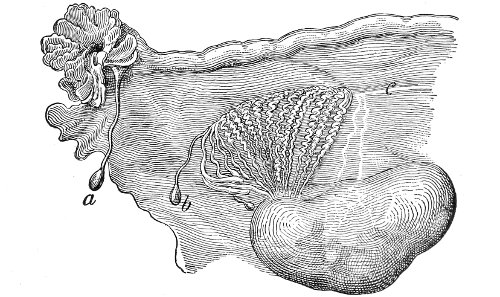

Suppuration of the vulvo-vaginal gland is accompanied by marked swelling and peripheral edema. The swelling may extend to the anus, and is of characteristic shape (Fig. 17). The pain is always severe. Fluctuation is first apparent on the inner surface of the labium majus. If the condition is not treated, one or more fistulous openings appear below the orifice of the duct, and the pus is discharged. The condition then becomes chronic. The fistulous openings persist. Acute inflammation disappears from the gland, leaving it in a condition of hypertrophic induration. A thin, milky or greenish, purulent fluid may be pressed out of the duct or the fistulous openings. Infection from this discharge may be communicated to man, or may ascend the genital 40 tract, producing inflammation of the endometrium or of the Fallopian tubes.

Fig. 17.—Abscess of right vulvo-vaginal gland.

In abscess of the vulvo-vaginal gland a free incision should immediately be made into the labium at the junction of the skin and the mucous membrane. The interior should be wiped out with pure carbolic acid and the cavity packed with gauze. If the disease is first seen in the chronic stage, after the abscess has evacuated itself, the only method of cure is to excise, with curved scissors, the whole of the indurated gland, the duct, and the fistulous tracts. The wound may be left open and packed, or it may be closed immediately with buried catgut sutures.